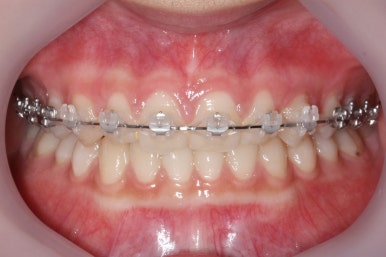

부산매복치아교정 상악 부분교정을 통해 매복치를 교정해준 이번 치료의 전후사진 비교입니다.

썩은 유치 대신 영구치 송곳니는 매우 자연스럽게 위치되었습니다. 아랫니는 교정하지 않았기 때문에 약간 삐뚠 느낌은 남아있지만 맞물림은 크게 문제가 없게 마무리 되었습니다.

얼굴 모습에서의 전후 비교입니다.

처음부터 매복치 이외에는 얼굴모습에서의 큰 문제가 없었고, 변화를 의도하지도 않았기 때문에 전후 모습의 큰 차이는 없습니다.

대신, 송곳니가 제위치되면서 웃거나 말할 때 미적으로 많이 개선된 것을 볼 수 있습니다.